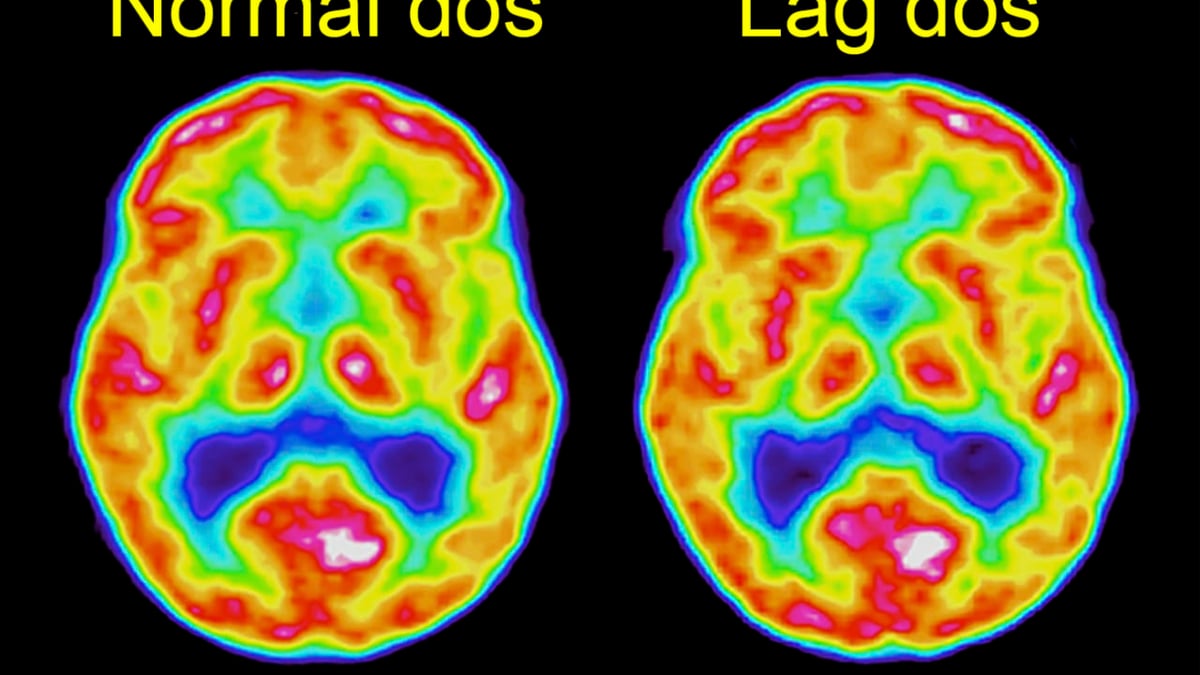

PET-avbildning av en frisk försöksperson med normal respektive hög dos.

Den metod för avancerad hjärnavbildning som används på Akademiska kallas FDG-PET och innebär att man använder radioaktivt socker (FDG) som spårämne. Vid en undersökning får patienterna normalt en dos som motsvarar det som en genomsnittlig svensk får under drygt ett år från bakgrundsstrålning och dylikt.